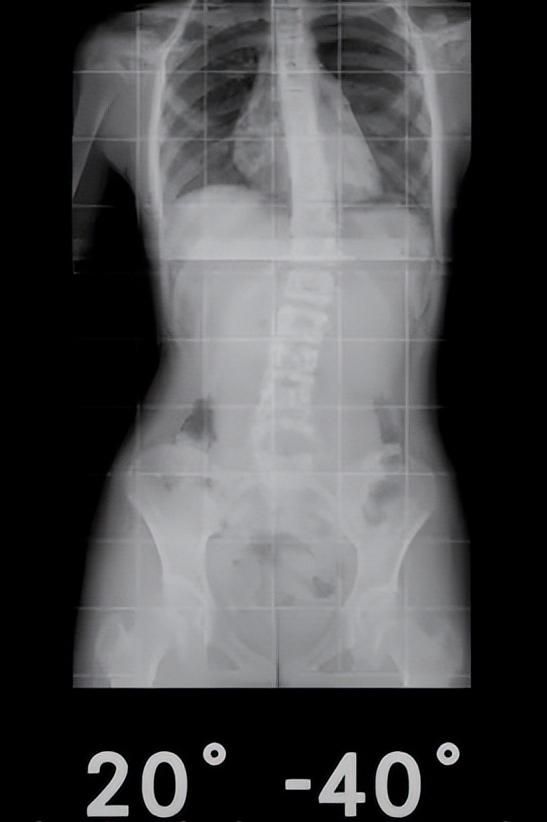

二、如何判断脊柱侧弯的严重程度?

X光显示0°-10°,10°-20°为轻微侧弯,一般25°一下相对就比较轻微,20°-40°是重度侧弯,40°以上就相对严重。